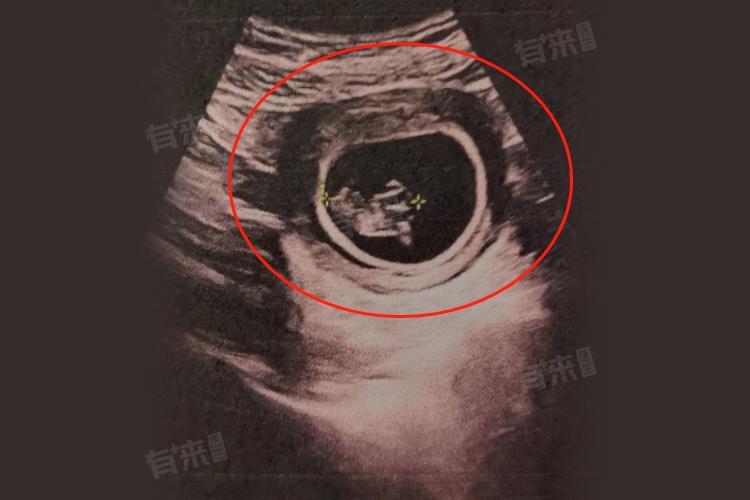

3、超声检查结果良好:在怀孕9周进行超声检查时,若胎儿稳定,会呈现出一系列正常的超声影像特征。首先,能清晰看到胎儿的胎芽和胎心搏动。胎芽的大小应与孕周相符,一般怀孕9周时,胎芽长度约为2.5厘米左右。胎心搏动有力且规律,正常的胎心频率在每分钟110-160次之间。这表明胎儿的心脏发育正常,能够为身体各器官提供血液循环,保障胎儿的生长发育。